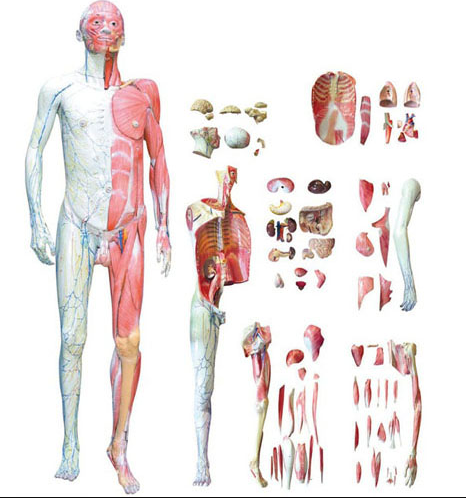

■ 尺寸:自然大(dà);

■ 部(bù)件:1部件;

■ 功能:模型是以研究女性骨盆解剖和了解之間的關係骨盆骨骼,肌肉和女性生殖器官。它(tā)顯示了一個(gè)完整的女性人體(tǐ)骨盆骨骼與韌帶(dài),肌肉(ròu),內(nèi)部和外部女性(xìng)泌尿生殖器(qì)官。膀胱和子宮都可以沿縱向平麵打開,以顯示其內部解剖結構。所有的結構都被複製得非常詳細和準確;

■ 材(cái)質:進口環保PVC材料,進口環(huán)保油漆。